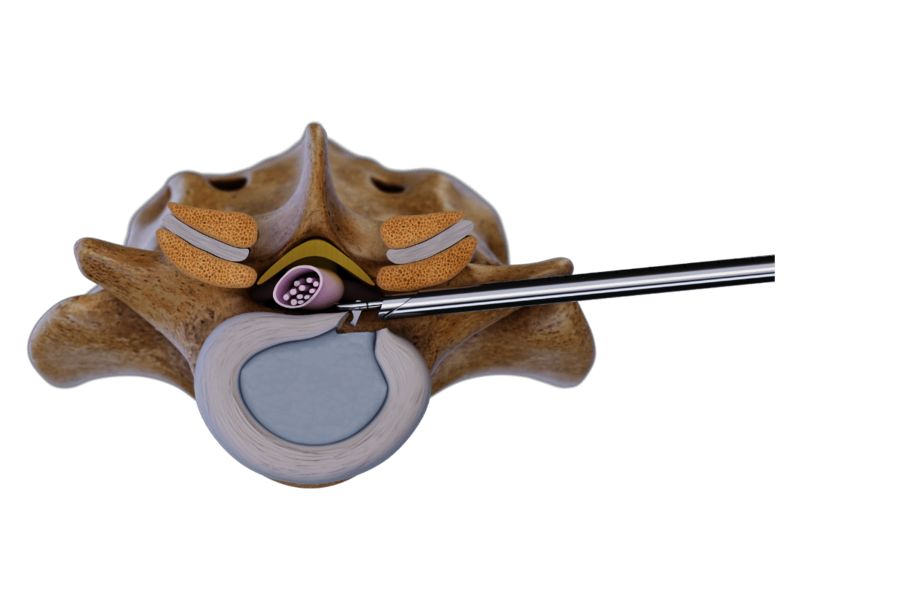

Trans-/extraforaminale Technik

Diese Technik nutzt das Foramen intervertebrale als Zugang zur Pathologie. Der Zugang wird unter Röntgenkontrolle mit einer Punktionskanüle geführt, gefolgt von der Dilatation und dem Einführen der Arbeitshülse.

Der Eingriff erfolgt unter kontinuierlicher Spülung mit hochauflösender endoskopischer Bildgebung. Spezialisierte Instrumente wie Zangen, Fräser und Stanzen gewährleisten einen effektiven und präzisen Eingriff.